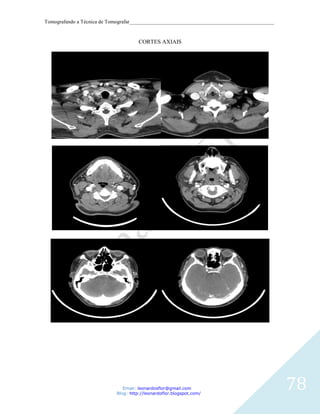

As posições para este exame são:

axial com cortes paralelos ao palato duro até o término do seio frontal.

coronal com cortes perpendiculares ao plano infra-órbito-meatal até o término do seio

esfenoidal.

SPN

Cortes Coronais – Prono e Supino